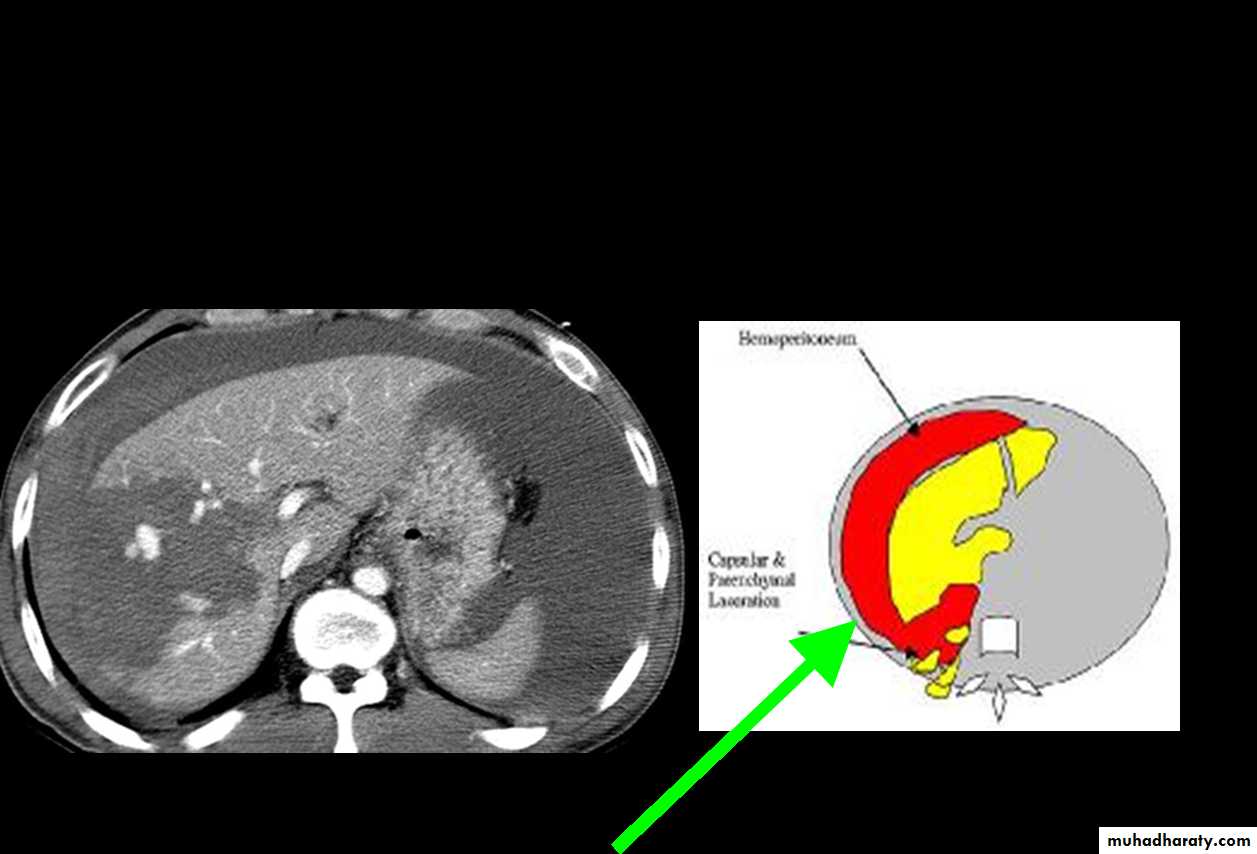

CT Scans

Accurate in localizing the site of liver injury and any associated injuries

Used to monitor healing

CT criteria for staging liver trauma uses AAST liver injury scaleGrades 1-6

Subcapsular hematoma

Laceration

Contusion

Hepatic vascular disruption